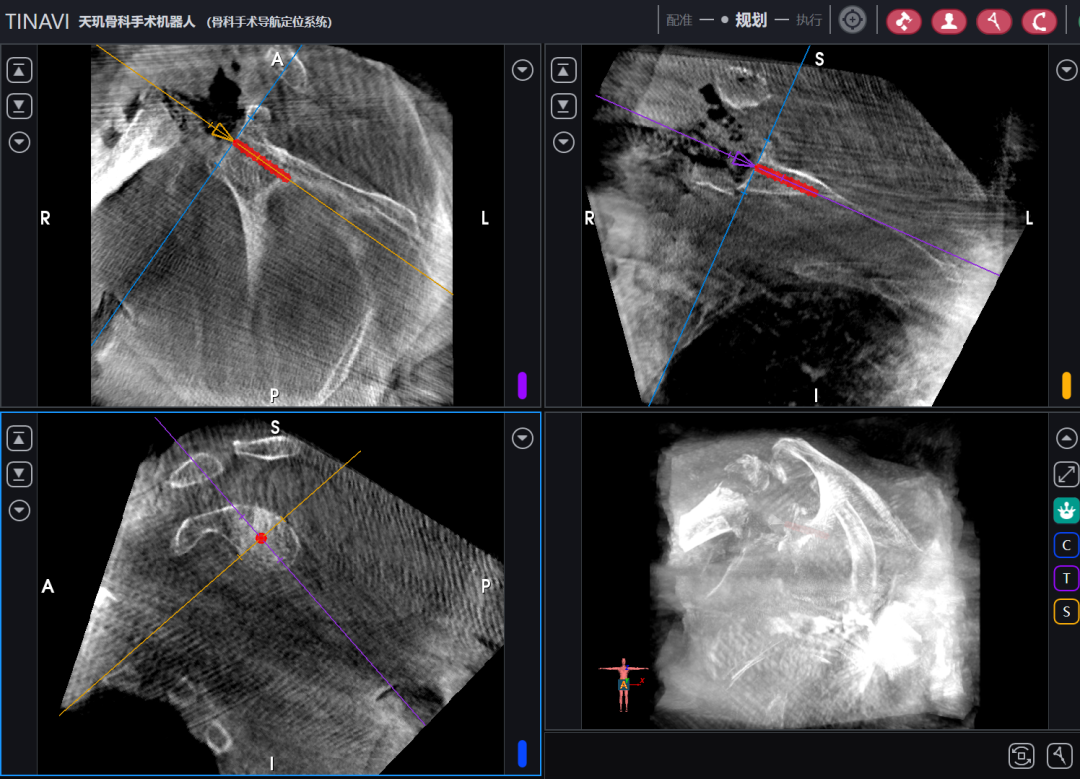

患者沙滩椅体位,手术使用胸肌三角肌入路,充分显露后常规进行肱骨侧和肩盂侧准备,在至关重要的肩盂侧基座导针置入步骤,在锁骨近端安放患者示踪器,使用术中三维影像设备获取肩关节三维图像,扫描结果传输至机器人导航系统,完成路径规划,并在机器人的引导下置入导针,置入后再次进行CT扫描验证,证实导针精确置入,完美符合预期。

团队成员韩巍主任医师介绍:“基座的准确安放是手术成功的关键,直接影响患者的功能结果和假体使用年限。传统的操作方式依赖医生根据经验手动完成,术中位置验证困难,所以客观性和精准度严重不足。这项创新的机器人辅助技术极大提高了手术的精准性和稳定性,将原本较为主观的评价方式客观化,能有效减少术中透视次数、缩短手术时间、降低手术风险。”